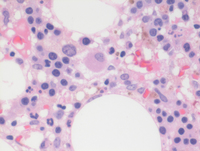

Bone marrow biopsy findings-higher power

Bone marrow biopsy at higher power demonstrates the mononuclear cells with evidence of dispersed chromatin compatible with blasts in the first two images. Paratrabecular clusters of blastic cells around the bone are also noted. The last image demonstrates a single dysplastic hypolobated megakaryocytes in the center of the field.